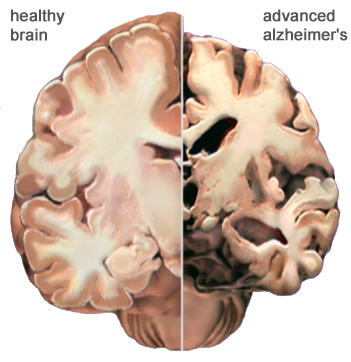

Σικάγο: Απεικονιστικές εξετάσεις ενδεχομένως να είναι ικανές να ανιχνεύσουν τα πρώιμα σημάδια της νόσου Αλτσχάιμερ πολύ πριν αρχίσει να επηρεάζει την μνήμη, γεγονός που μπορεί να συντελέσει σε πρώιμη διάγνωση και πιο αποτελεσματικά θεραπευτικά σχήματα.